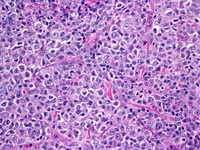

Follicular Lymphoma Grade 3A

Follicular Lymphoma Grade 3A. Follicular lymphoma (fl), grade 3, is recognized as a distinct entity in the world health organization classification of lymphoma. Centroblasts with large round vesicular nuclei and prominent nucleoli make up the dominant cell type;

Follicular lymphoma, grade 3B 9

Grade 3 has molecular and genetic characteristics that distinguish it from other grades of fl. Symptoms of stage 3 lymphoma. Bcl2 & ki67 in follicular lymphoma grade 3a.

Centroblasts with large round vesicular nuclei and prominent nucleoli make up the dominant cell type; There are various treatment options for fl based on the severity of associated symptoms and the rate of cancer growth. Grade 3 has molecular and genetic characteristics that distinguish it from other grades of fl.

I found a lump at the top of my groin which i thought was a muscle tear so i went to the gp. It is further classified into grade 3a and grade 3b depending on the bernard cell counting system and percentage of centroblasts. 129 cases were grade 1 or 2, 44 grade 3a, and 13 grade 3b.

The histologic grade of fl depends on the number of centroblasts and. Symptoms of stage 3 lymphoma. Grade 3a is usually also regarded as low grade fl although some studies have regarded it as high grade fl;